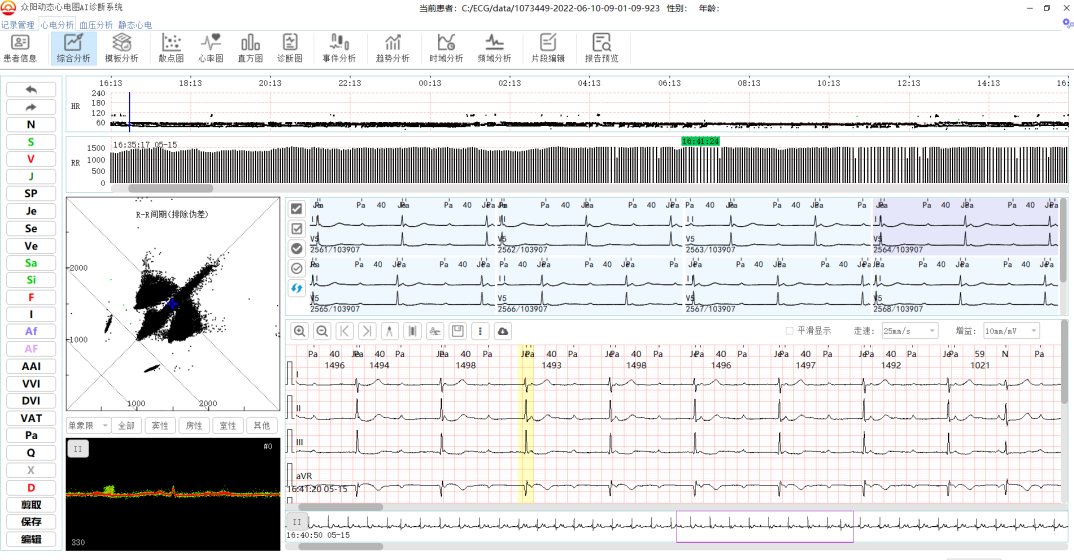

应用案例